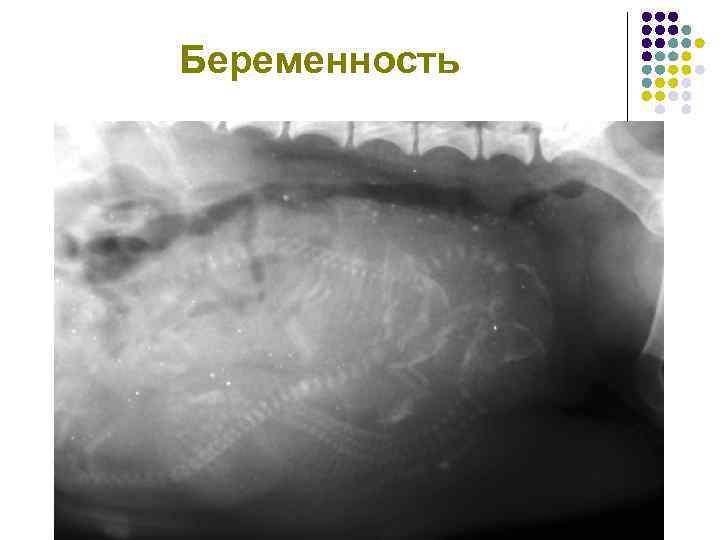

Беременность